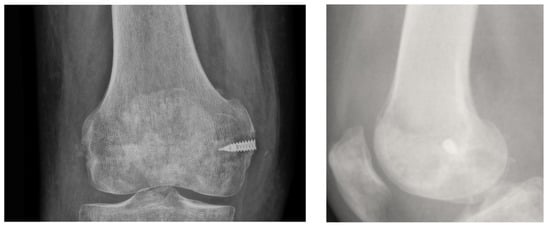

Thirty-three patients (41 implants) underwent operative intervention with procedures that required the implantation of a suture anchor. Of the 33 patients, 27 had one implant (27 implants), five had two implants (10 implants), and one had four implants (Figure 1).

Figure 1. Quadriceps reconstruction after its rupture by mean of 4 TWINFIX.